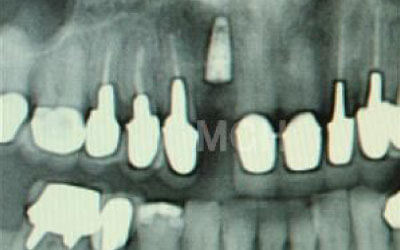

今回のご質問ですが、抜けた部分の骨が薄いなどの理由で「インプラントはできない」と言われた可能性があります。

前歯はもともと骨が薄く、歯が抜けると時間の経過とともにさらに骨が痩せてきてしまうので、インプラント治療の難易度が高い場所です。

ただ結論からお話すると、インプラント治療は可能です。

なぜなら、もし仮に骨が薄くても、骨の治療によって厚みが増せば、安全にインプラント治療が行えるからです。